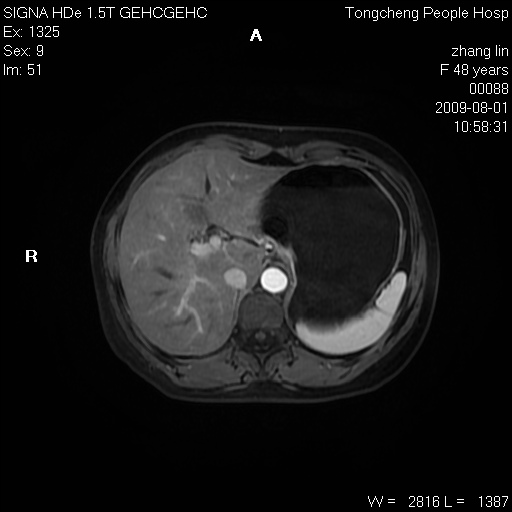

女,48岁。健康体检,彩超发现右肾占位性病变。平素健康。

临床诊断:右肾占位性病变,性质待定(囊肿?肿瘤?)。

上中腹部mr平扫+增强扫描,图像如下:

右肾上极见一类圆形病灶,t1wi呈等信号t2wi呈等高混杂信号,三期增强无强化,边界清---考虑囊肿出血。

同反相位均表现为等信号,病变无强化,考虑含蛋白的囊肿可能,弥散加权相或许有些帮助,

肝囊肿

慢性胆囊炎